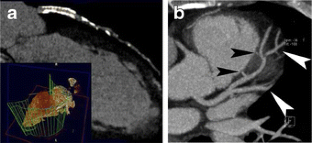

Fig 7.

Fig 8.